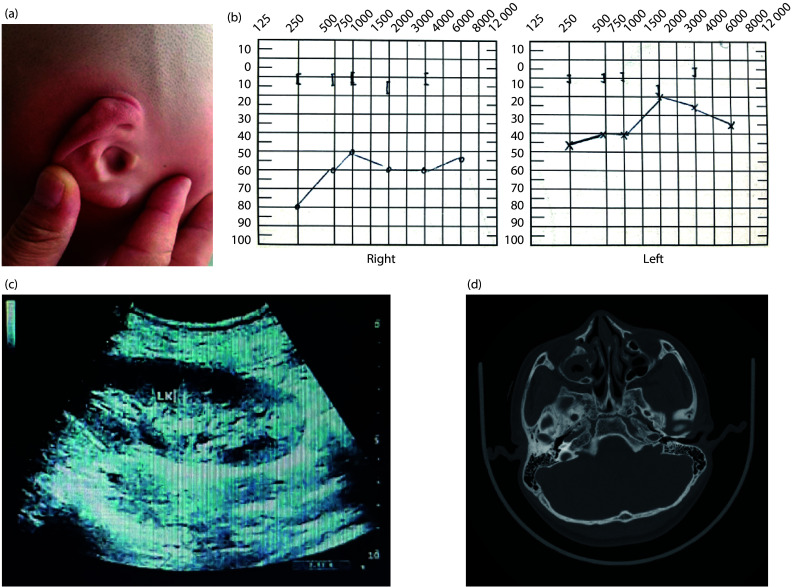

耳肾分支综合征是一种罕见的常染色体显性遗传病。其主要临床表现为鳃裂囊肿、耳前瘘、听力障碍、肾脏畸形等。BOR综合征与杂合致病性变异相关,包括EYA1、SIX1和SIX5。该研究以一名13岁的中国男孩为研究对象,该男孩表现为听力障碍、肾脏畸形和右外耳道骨性闭锁伴小耳症。男孩的临床表现符合BOR综合征的诊断标准。男童的两名家庭成员接受了临床检查。然而,两者均未显示出与BOR综合征相关的表型。男孩和他的两个亲戚提供了血液样本,用于提取基因组DNA,然后进行桑格测序。在男孩身上发现了一种新的GREB1L基因突变,但他的家庭成员都没有表现出相同的变异。发现一个新的GREB1L突变为了解BOR综合征的基因型-表型相关性提供了有价值的见解,提高了早期诊断的准确性,促进了个性化治疗策略的发展。

Branchio-oto-renal (BOR) syndrome is an uncommon disorder inherited in an autosomal dominant manner. Its main clinical manifestations include branchial cleft cysts, anterior auricular fistula, hearing impairment, and kidney malformations. BOR syndrome is associated with heterozygous pathogenic variants including EYA1, SIX1, and SIX5. The study focused on a 13-year-old Chinese boy who presented with hearing impairment, renal malformations, and bony atresia of the right external auditory canal with microtia. The boy's clinical manifestations met the diagnostic criteria for BOR syndrome. Two of the boy's family members underwent clinical examination. However, neither displayed a phenotype associated with BOR syndrome. The boy and his two relatives provided blood samples for genomic DNA extraction, followed by Sanger sequencing. A novel mutation in the GREB1L gene was identified in the boy, but neither of his family members exhibited the same variant. Identifying a novel mutation in GREB1L offers valuable insights into the genotype-phenotype correlation of BOR syndrome, improving the precision of early diagnosis and promoting the advancement of personalized treatment strategies.